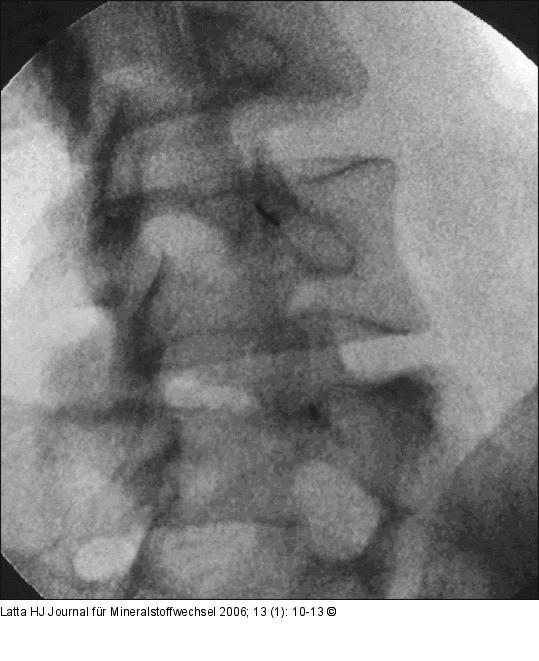

Abbildung 2a: Facettengelenke - Intraartikuläre Infiltration Intraartikuläre Infiltration der Facettengelenke L4/L5 u. L5/S1 rechts ohne KM. |

Intraartikuläre Infiltration der Facettengelenke L4/L5 u. L5/S1 rechts ohne KM. |